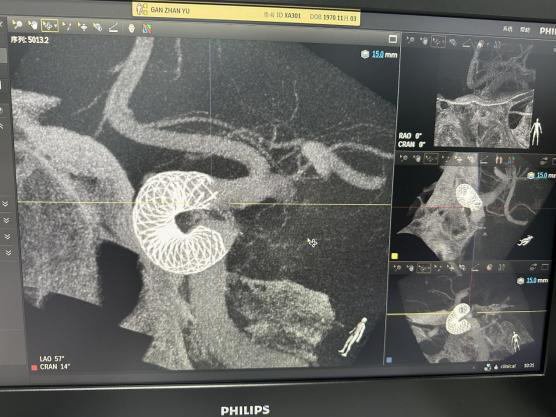

密网支架(血流导向装置)治疗颅内动脉瘤效果:

转归参考: